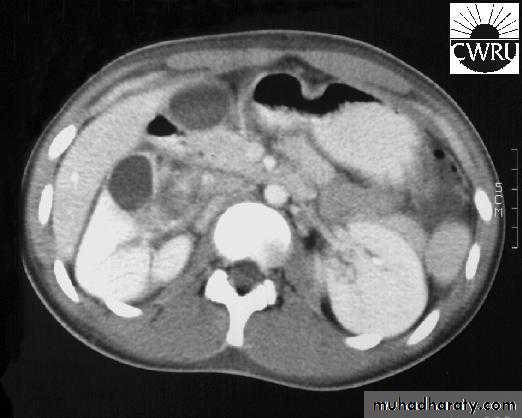

Perinephric abscessInfection and pus collection in the perinephric space within Gerota’s fascia

CT scan & MRI: diagnostic.

Drinage of perinephric abscess